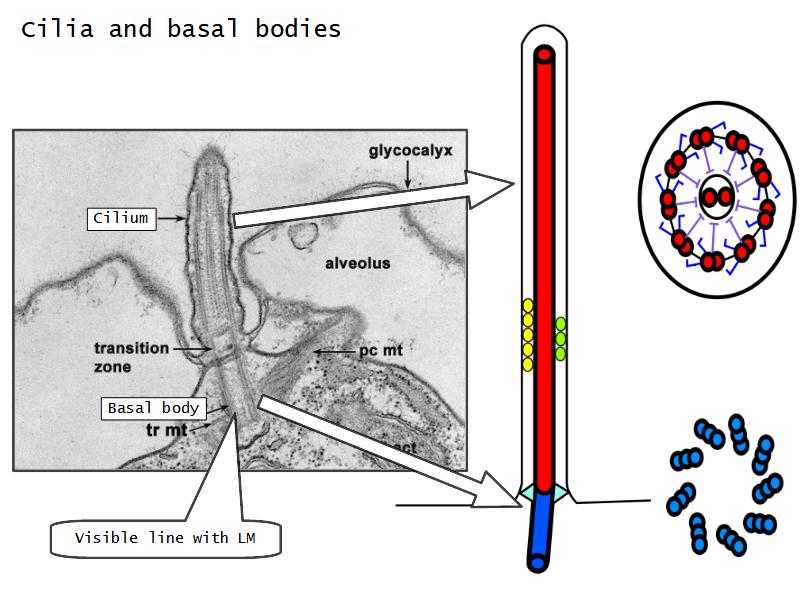

Respiratory epithelium

- Pseudostratified

- Ciliated

- Columnar

- Epithelium with

- 4 Cells

- Ciliated columnar cells

- Non-ciliated columnar cells

- Goblet cells

- Basal cells